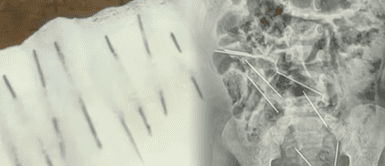

¡Casi no la cuenta! Menor de dos años se traga ocho agujas y médicos le salvan la vida. Menor de dos años salva de morir tras ingerir 8 agujas de inyectables en Tarapoto. El menor fue llevado de inmediato al hospital, siendo salvado por los médicos, quienes indicaron que el menor presentaba fuertes dolores. Dos de las agujas, ubicadas entre la vejiga y el recto, pusieron en riesgo su vida

Médicos salvan de morir a menor de dos años quien se comió 8 agujas en Tarapoto.